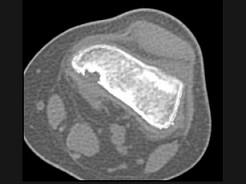

问题 男,12岁,大腿下部间歇性疼痛,劳累后加重,结合图像,最可能的诊断是 ( )

选项 A、邻皮质软骨瘤 B、非骨化性纤维瘤 C、干骺端结核 D、骨样骨瘤 E、纤维性骨皮质缺损

答案 E